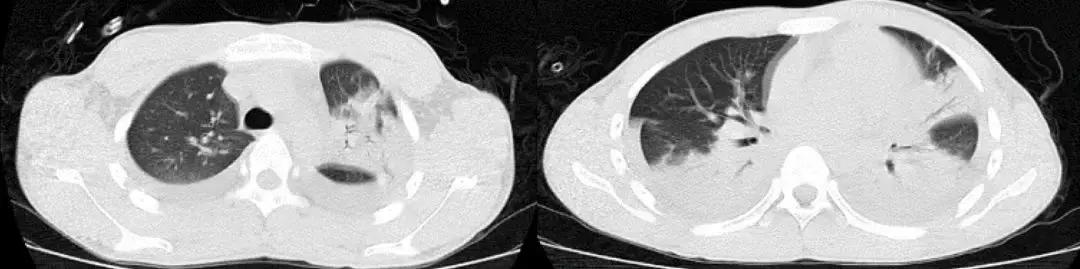

1天前急救车于我院急诊,血常规提示白细胞明显升高,胸部CT(2017-3-15):两肺感染,右肺上叶中叶膨胀不全,两肺间质改变,两肺肺气肿;急诊给予「头孢哌酮舒巴坦联合万古霉素」抗感染治疗,面罩10L/分吸氧维持血氧饱和度在85~95%之间,现为进一步诊治以「重症肺炎」收住我科。

CT:2018-3-15

2017-9-26

2017-9-29